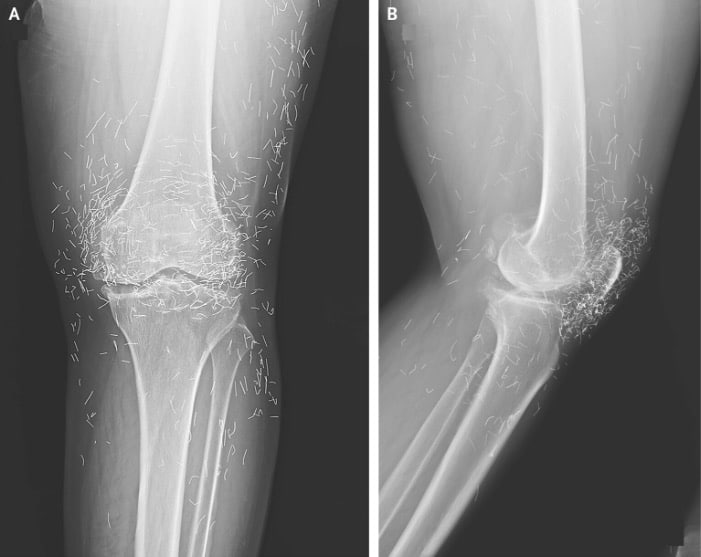

Years later, when doctors took X-rays to evaluate her knee condition, they weren’t prepared for what appeared on the images. Her knees were filled with dozens of bright, metallic flecks — tiny needles embedded deep within the joint area.

The findings were later documented in a case published by the New England Journal of Medicine.

Beyond inflammation, the needles created another problem: imaging complications. Metal objects can obscure parts of the anatomy on X-rays, making it harder for doctors to clearly assess joint damage or disease progression.